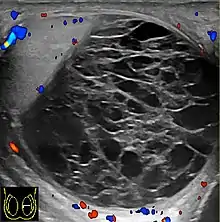

Rhabdomyosarcoma (a) Longitudinal section (composite image) of high resolution ultrasound of a 14-year-old boy shows a well defined hypoechoic extratesticular mass is found in the left scrotum, hydrocele is also present. (b) Color Doppler ultrasound shows that the mass is hypervascular.

Rhabdomyosarcoma is the most common tumor of the lower genitourinary tract in children in the first two decades, it may develop anywhere in the body, and 4% occur in the paratesticular region which carries a better outcome than lesions elsewhere in the genitourinary tract. Clinically, the patient usually presents with non-specific complaints of a unilateral, painless intrascrotal swelling not associated with fever.

Transillumination test is positive when a hydrocele is present, often resulting in a misdiagnosis of epididymitis, which is more commonly associated with hydrocele. The ultrasound findings of paratesticular rhabdomyosarcoma are variable. It usually presents as an echo-poor mass [Fig. 11a] with or without hydrocele. With color Doppler sonography these tumors are generally hypervascular.